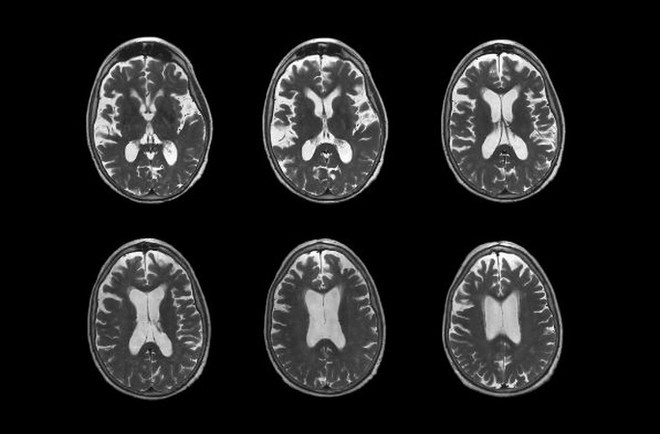

Mỹ: FDA cấp phép lưu hành thuốc Leqembi chữa bệnh Alzheimer ảnh 1Thuốc Leqembi được khuyến cáo sử dụng cho những bệnh nhân ở giai đoạn đầu và nhẹ của bệnh Alzheimer. (Nguồn: The New York Times)